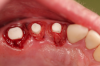

Fig 1. Preoperative surgery.

Figure 1

Fig 2. Extractions and immediate placement.

Figure 2

Figure 1 and Figure 2 depict the preoperative image and subsequent removal of three posterior teeth, immediate placement of zirconia-oxide ceramic dental implants, and soft-tissue augmentation with platelet-rich fibrin (PRF) to enhance the soft-tissue architecture surrounding the ceramic implants. The teeth were removed atraumatically and without suture placement. Because the implants were one-piece in stature (the abutment was incorporated into the implant), the recommendation was to splint the multiple units to minimize the lateral forces from mastication, swallowing, and tongue movement.